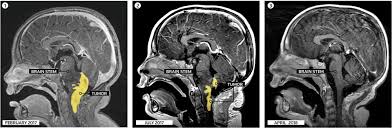

Childhood brain stem glioma is a disease in which benign (noncancer) or malignant (cancer) cells form in the tissues of the brain stem. The signs and symptoms of brain stem glioma are not the same in every child. Cancer can be hard to detect in children. Still, cancer is the second leading cause of death in children younger than 15 years old, after accidents. Spinal cord tumors are less common than brain tumors in both children and adults. Children with cancer may experience a variety of the signs or symptoms listed below, many of which are similar to common childhood illnesses. Keep in mind, headaches are not usually early warning signs, but can occur once a tumor has reached a considerable size. You can detect brain tumor in your child with the help of some signs and symptoms. When a child develops a brain tumor, early diagnosis is essential. In children, tumors usually start in a part of the brain that controls movement and coordination. Secondary brain tumors are made up of cells that have metastasized to the brain from somewhere else in the body. Research indicates that prolonged, severe headaches that seem to worsen early in the morning or during physical activity could be a potential sign of brain cancer. The signs and symptoms of brain tumors vary widely, but include:

There are two types of brain stem gliomas in children. For example, if a brain tumor is located in the cerebellum at the back of the head, a child may have trouble with movement, walking, balance and coordination. When a child develops a brain tumor, early diagnosis is essential. Around 500 children are diagnosed with a brain tumour every year, and these make up 34 per cent of all childhood cancer deaths. Headaches that get worse over time are a common symptom of brain tumors.